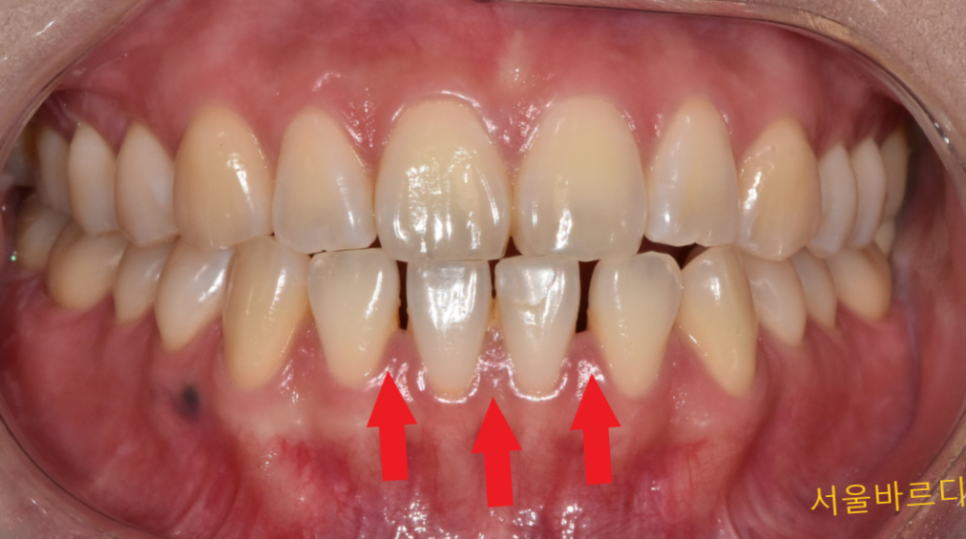

벌어진 아래 앞니로 인해

공간이 보이는 곳은 3부분 이었습니다.

제가 판단했을 때 상대적으로 가운데 치아 2개가

작아 2개 정도만 치료해도

벌어져 보이는 것을 해결할 수 있다 생각했습니다.

231027

환자분께는 그림을 그려

앞니 라미네이트로 공간을 메우게 될 것이다

치료 방향을 설명드렸죠.

치료를 하기 전 까지는 치아 틈새가 어떻게 메꿔질지

예측이 쉽지 않기 때문에

그림을 그려 설명을 드리고 있습니다.